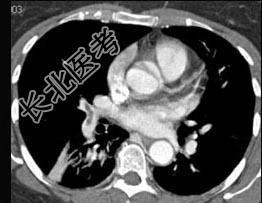

- 单项选择题男,56岁, 食管癌术后,胸痛, 呼吸困难,结合CT图像, 最可能的诊断是 ( )

A、食管癌肺转移

B、肺栓塞

C、支气管扩张

D、肺水肿

E、肺不张